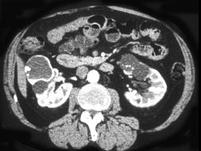

女,34岁,请根据所示图像,选择最可能诊断 ( )A、双肾多发囊肿并钙化B、囊性肾癌C、单纯性肾囊肿D、双肾多发单纯性肾囊肿E、多囊肾

问题 女,34岁,请根据所示图像,选择最可能诊断 ( )

选项 A、双肾多发囊肿并钙化 B、囊性肾癌 C、单纯性肾囊肿 D、双肾多发单纯性肾囊肿 E、多囊肾

答案 A